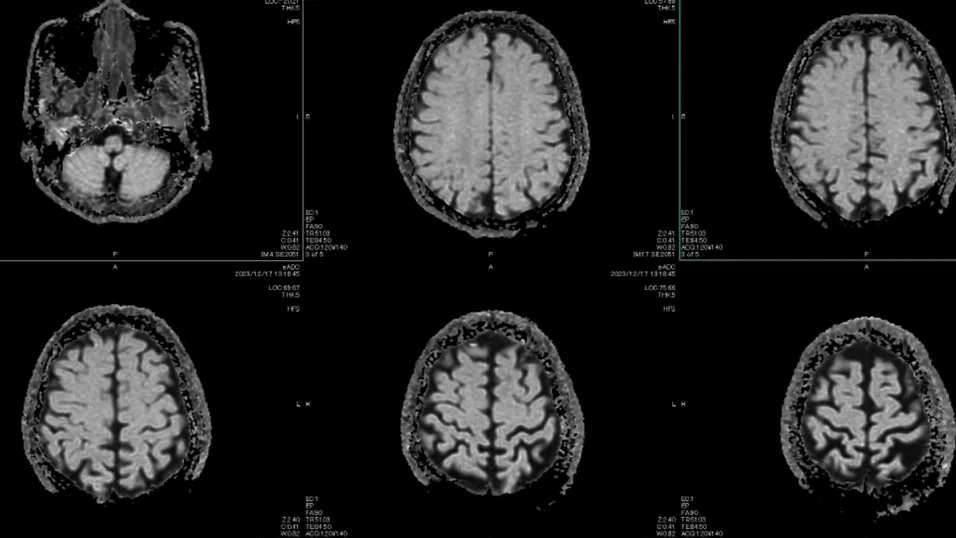

Проучването, базирано на мозъчни сканирания на близо 4 000 души на възраст от под една година до 90, картографира невралните връзки и тяхната еволюция през живота ни

Проучването, базирано на мозъчни сканирания на близо 4 000 души на възраст от под една година до 90, картографира невралните връзки и тяхната еволюция през живота ни, пише Guardian. Така се разкриват пет фази, разделени от четири ключови „повратни момента“, в които организацията на мозъка преминава към различна траектория – приблизително около 9, 32, 66 и 83 години.

Учените измерват организацията на мозъка чрез 12 различни параметъра, включително ефективността на свързаността, степента на разделение на мрежите и това доколко мозъкът разчита на централни възли или на по-дифузна структура.